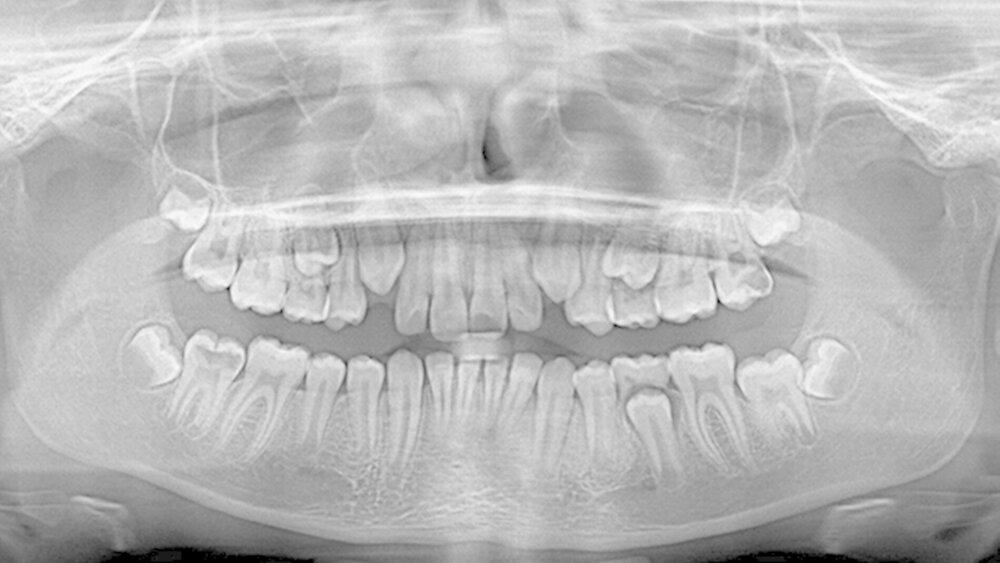

Röntgenbefund:Am 16. Juni 2015 wurde im Rahmen der Erstberatung in unserer Praxis eine Panoramaschichtaufnahme des Patienten angefertigt (Abbildung 2). Die Aufnahme zeigte an Zahn 27 eine mindestens zwei Drittel des koronalen Dentins umfassende Transluzenzzone, angrenzend an die disto-okklusale Schmelz-Dentin-Grenze. Als weiterer Befund war im ansonsten radiologisch unauffälligen Wechselgebiss an Zahn 47 ebenfalls eine große Transluzenzzone im nahezu gesamten koronalen Dentin sichtbar. (Dieser Zahn war bei der visuellen Befundung klinisch noch nicht in der Mundhöhle sichtbar.)

Der vorliegende Fall zeigt eindrucksvoll verschiedene Stadien der präeruptiven koronalen Resorption (PIR): eine präeruptiv im Röntgenbild sichtbare Transluzenzzone im Dentin des Zahns 47 an der koronalen Schmelz-Dentin Grenze mit intaktem Schmelzmantel und eine große Kavitätenbildung nach Durchbruch des Zahns 27 in die Mundhöhle.

Passend zu vorherigen Studien, die ein langsames Voranschreiten des Prozesses beschreiben, solange der Zahn noch keinen Kontakt zum Biofilm der Mundhöhle hat, setzt eine rapide Progression der Zerstörung nach Besiedelung der Oberfläche mit kariösen Mikroorganismen ein [Seow, 1998]. Dazu passt auch die klinische Symptomatik bei unserem Patienten kurz nach Durchbruch des Zahns 27.